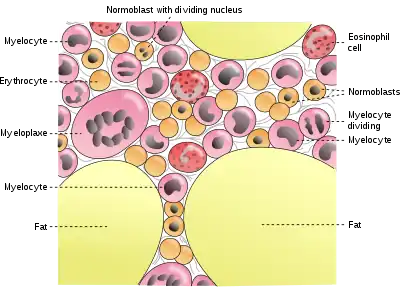

Bone marrow, also known as myeloid tissue in red bone marrow, can be found in almost any bone that holds cancellous tissue. In newborns, all such bones are filled exclusively with red marrow or hematopoietic marrow, but as the child ages the hematopoietic fraction decreases in quantity and the fatty/ yellow fraction called marrow adipose tissue (MAT) increases in quantity. In adults, red marrow is mostly found in the bone marrow of the femur, the ribs, the vertebrae and pelvic bones.[19]

Synthetic

The cancellous part of bones contain bone marrow. Bone marrow produces blood cells in a process called hematopoiesis.[50] Blood cells that are created in bone marrow include red blood cells, platelets and white blood cells.[51] Progenitor cells such as the hematopoietic stem cell divide in a process called mitosis to produce precursor cells. These include precursors which eventually give rise to white blood cells, and erythroblasts which give rise to red blood cells.[52] Unlike red and white blood cells, created by mitosis, platelets are shed from very large cells called megakaryocytes.[53] This process of progressive differentiation occurs within the bone marrow. After the cells are matured, they enter the circulation.[54] Every day, over 2.5 billion red blood cells and platelets, and 50–100 billion granulocytes are produced in this way.[22]

As well as creating cells, bone marrow is also one of the major sites where defective or aged red blood cells are destroyed.[22]

Cells in bone marrow